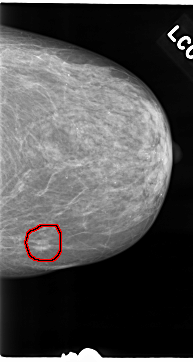

C_0049_1.LEFT_CC

LEFT_CC LINES 4696 PIXELS_PER_LINE 2504 BITS_PER_PIXEL 12 RESOLUTION 50 OVERLAY

FILE: C_0049_1.LEFT_CC.OVERLAY

TOTAL_ABNORMALITIES 1

ABNORMALITY 1

LESION_TYPE MASS SHAPE IRREGULAR MARGINS SPICULATED

ASSESSMENT 5

SUBTLETY 5

PATHOLOGY MALIGNANT

TOTAL_OUTLINES 1

BOUNDARY